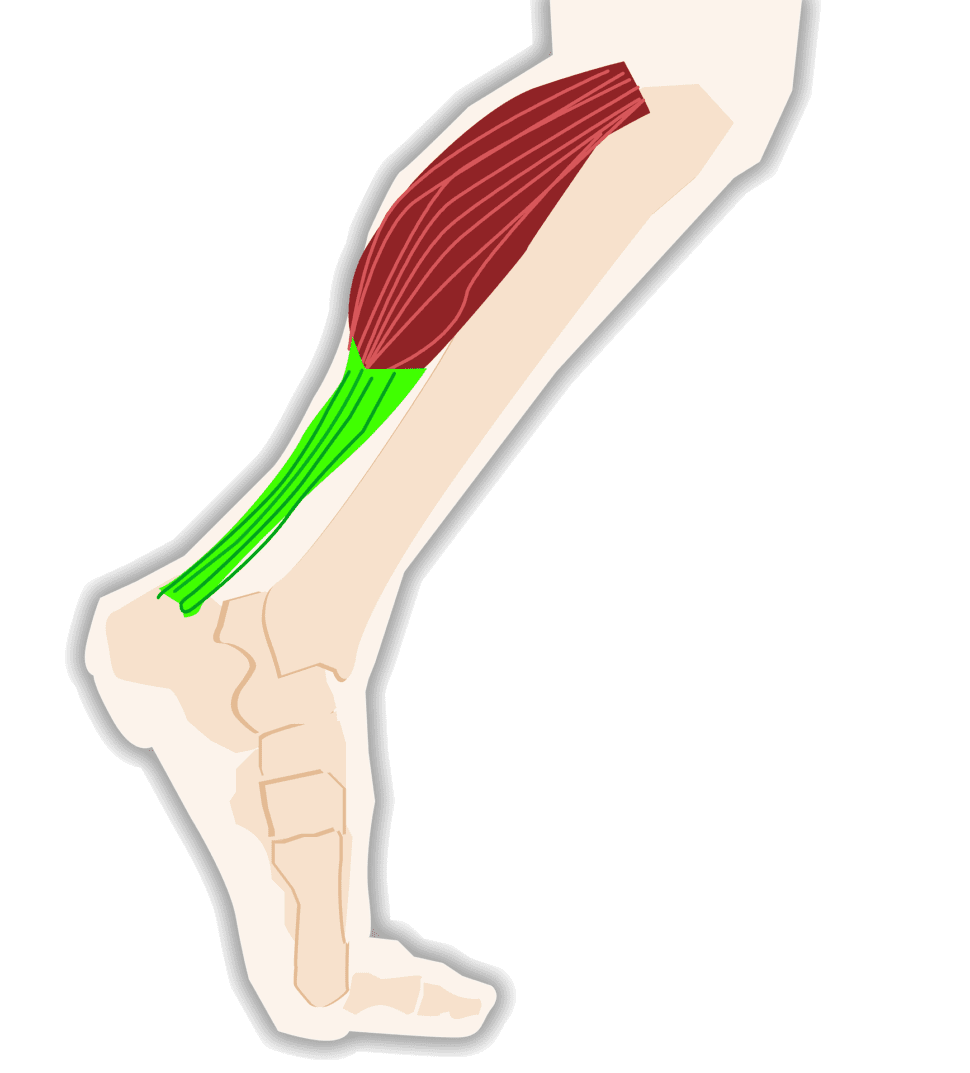

Achilles Tendon – Squat University

Achilles Tendon – NJSM

Achilles Tendon Diagram – 1000+ images about medical anatomy on …